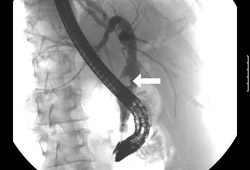

- colangiopancreatografía retrógrada endoscópica (CPRE)